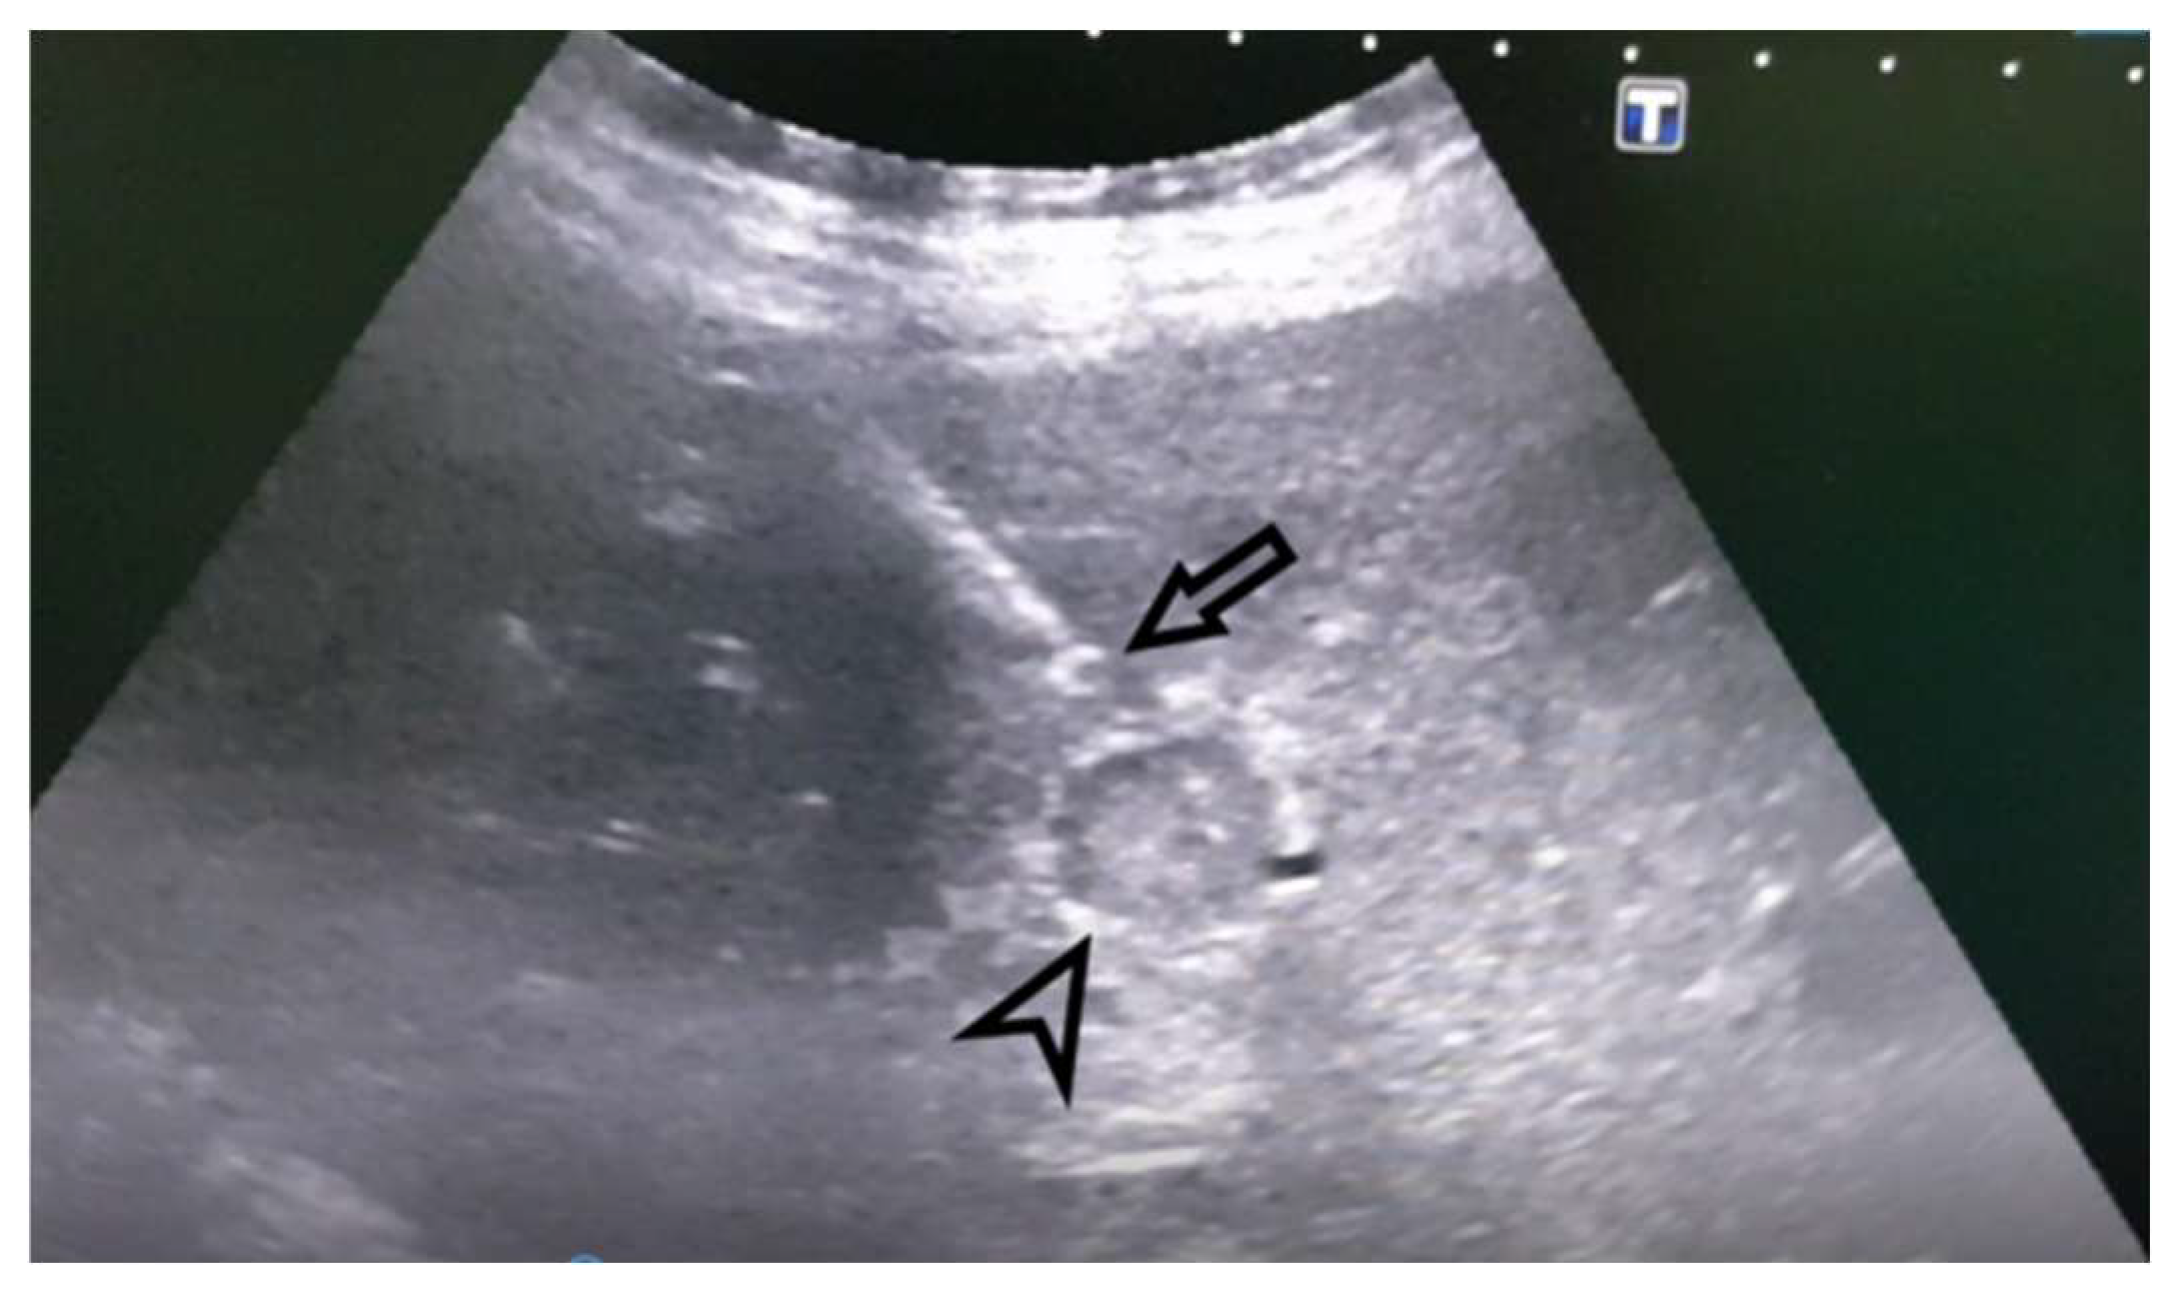

Figure 2. Ultrasound. Percutaneous core biopsy of the PVT of the right branch of the portal vein. The image shows the tip of the biopsy needle just in front of the PVT - indicated by the arrow, the PVT indicated by the arrowhead.

Case 1: A 72-year-old female, hospitalized for diarrhea and occasional abdominal pain for the last two months, followed by a loss of appetite and subsequent weight loss. PVT was detected ultrasonographically and in an enlarged, heterogeneous liver without a well-defined tumor mass. Abdominal MDCT has shown changes in the right liver lobe morphology, signs of PVT, ascites, and retroperitoneal lymphadenopathy (Figure 1). An MRI examination could not be performed due to the presence of the patient’s implants. AFP levels were significantly increased. A CNB was performed via the anterior abdominal wall, obtaining three samples from the right liver lobe, proximally to PV, and two pieces from the portal vein thrombus (Figure 2 and Figure 3). Pathohistological findings confirmed a poorly differentiated HCC in PVT samples. The other three samples did not provide any signs suggestive of HCC. Following a successful diagnosis, the oncological treatment could begin.